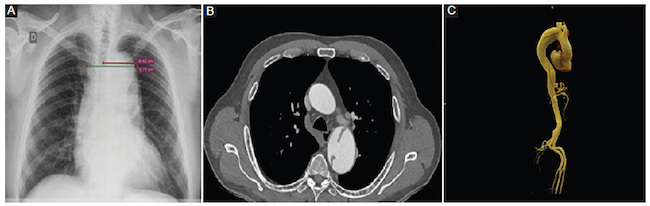

Ancho mediastínico máximo: definido por la distancia máxima del borde lateral derecho al borde lateral izquierdo del mediastino superior a nivel del botón aórtico (Figs. 1 y 2).

Ancho mediastínico izquierdo: definido por la distan-cia máxima tomada desde la línea media de la tráquea al borde lateral izquierdo del mediastino a nivel del cayado aórtico (Figs. 1 y 2).

El diagnóstico tomográfico de DA se realizó teniendo en cuenta los siguientes criterios: presencia de colgajo de disección, desplazamiento interno de las calcificaciones de la íntima, colgajo de la íntima visible, evaluación de la presencia de complicaciones (rotura hacia mediastino-pleura-pericardio, extensión y compromiso de ramas principales). Se clasificó la DA, según los criterios de Stanford, en tipo A (con involucro de la aorta ascendente) o tipo B (distal a la arteria subclavia izquierda)

Se calculó una media para el ancho mediastínico máximo de 9,6 cm y para el ancho mediastínico izquierdo de 7 cm en pacientes con DA. En los pacientes sin DA, la media del ancho mediastínico máximo fue de 8,1 cm y la del ancho mediastínico izquierdo de 5 cm (Tabla 3).